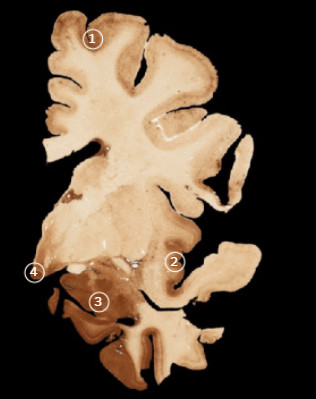

(下图左边是普通大脑,右边是患有CTE大脑)

在橄榄球员上,Tau蛋白的堆积和分布非常异常,

阻碍了正常的神经通路。

博士发现,这种蛋白异常主要出现在:

大脑前额叶,这里主要控制人的记忆力和抽象思维能力…

杏仁核,产生和调节情绪的地方…

岛叶,控制自我意识…

乳头状体,控制记忆的地方…

这些地方受损,导致了橄榄球员行为、情绪和心智上的问题,

也病变成慢性创伤性脑病(CTE)。